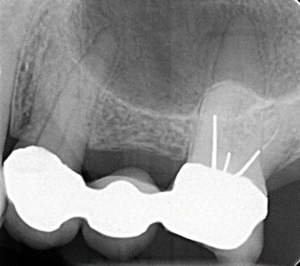

Clinical Cases